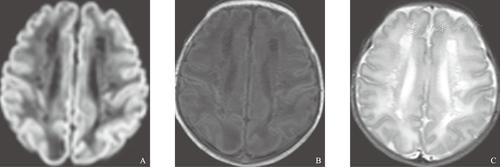

脑白质病变影像诊断

脑白质成像影像特征与常规mri比较

脑白质脱髓鞘